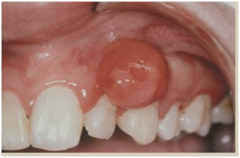

mucocele

-localized tissue swelling that increases and decreases in size most commonly on lower lip -severed salivary gland duct -mucous filled